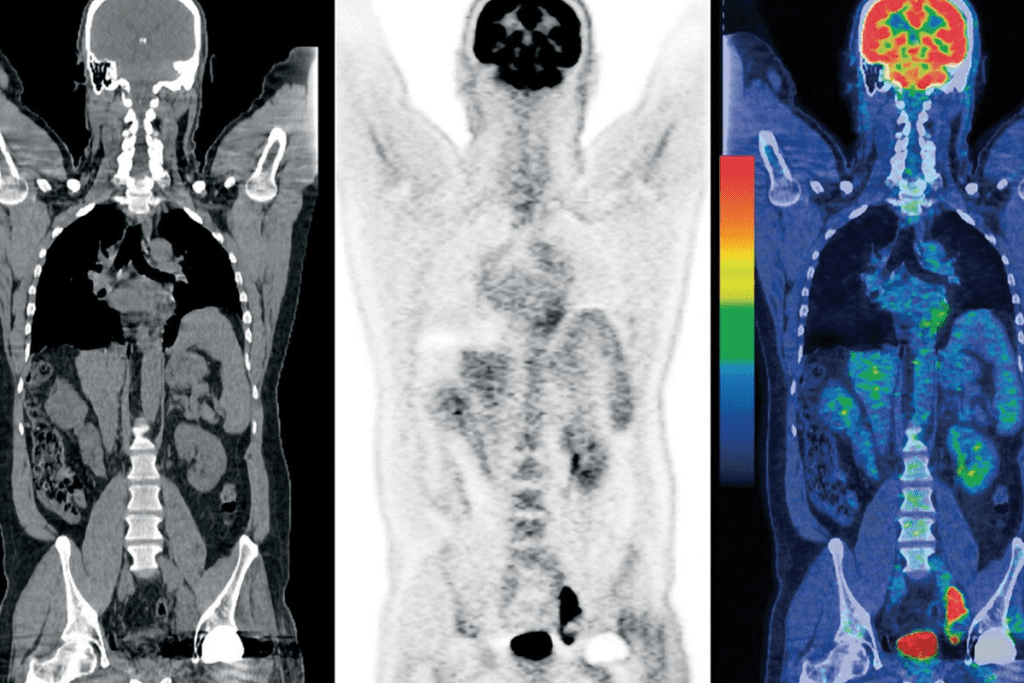

PET CT scans are a big step forward in medical imaging. They give a detailed look at the body’s inside parts and how they work. This tool mixes Positron Emission Tomography (PET) and Computed Tomography (CT) to show many health issues clearly.

A PET CT scan is a test that combines PET and CT scans. It shows detailed info about the body’s inside parts and how they work. PET CT imaging helps find and watch many health problems, like cancer, brain issues, and heart disease.

The goal of PET CT imaging is to get a better diagnosis. It mixes the PET scan’s functional info with the CT scan’s body details. This helps doctors spot problems better and plan treatments that work well.

Difference Between PET, CT, and Combined PET CT Scans

PET scans look at how the body uses certain chemicals. They’re great for finding cancer because cancer cells use more chemicals than normal cells.

CT scans show detailed pictures of the body’s inside parts, like organs and bones. They’re good for finding physical problems, like tumors or injuries.

Combined PET CT scans mix the PET scan’s info with the CT scan’s pictures. This gives a full view of the body’s inside and how it works. It makes diagnosing better and helps plan treatments that work.